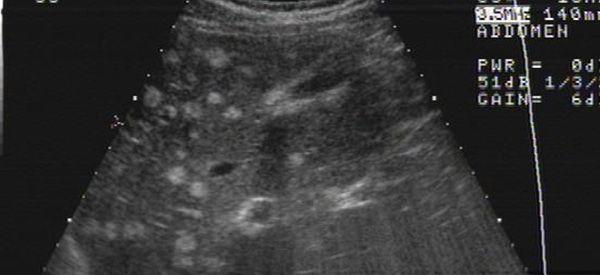

这种现象是有可能出现的,因为肝功能检查结果并不能保证肝脏的生理活动是完全正常的,所以在实际判断肝脏疾病的时候需要结合影像学等手段配合使用,项肝弥漫现象就是一种明显的影像学疾病。

肝弥漫可以通过影像学检查出来

肝弥漫是病毒侵袭肝脏的表现